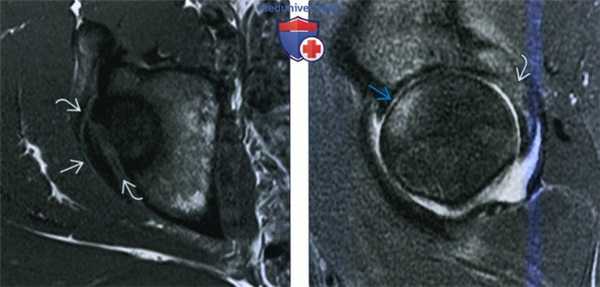

(Слева) МРТ Т1, аксиальный срез: у футболиста с болью после получения травмы, определяется гипоинтенсивный полулунный осколок задней стенки вертлужной впадины. Осколок перелома немного смещен.

(Справа) MPT, STIR, сагиттальный срез: у этого же пациента определяется выпот в полость сустава, отек головки бедренной кости спереди. Эти признаки указывают на ушиб с повреждением вышележащего хряща, а также на отек в месте перелома задней вертлужной впадины. Данные признаки служат критерием транзиторного заднего вывиха.